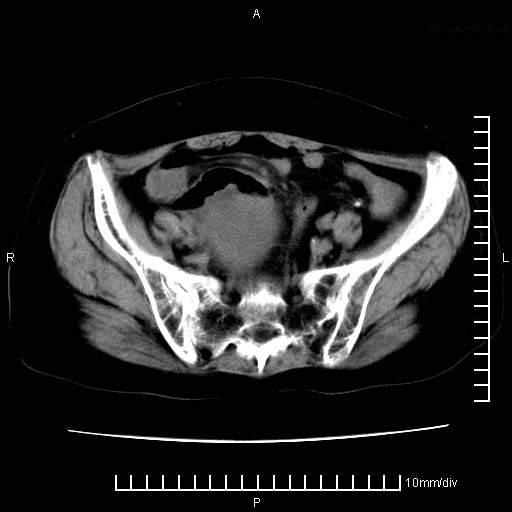

标题: CT24821:女性,70岁

下腹疼痛2月,加重并呕吐2天,下腹压痛,反跳痛。白细胞1万2.

下腹至盆腔较大包块,与邻近肠管关系密切,下腹疼痛2月,加重并呕吐2天,下腹压痛,反跳痛。白细胞1万2.

由于没有做肠道准备很难分清是哪根肠管,但看位置考虑为升结肠回盲部的问题,我首先考虑化脓性阑尾炎,不除外结肠癌合并感染化脓。建议做增强进一步明确。

补充:道格拉斯腔内有积液,且密度较高,显然提示有感染。